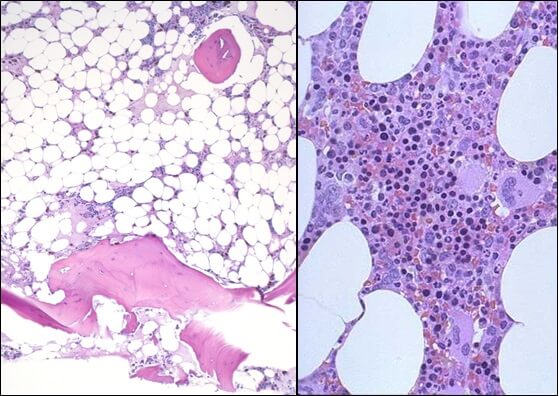

In this disease, the bone marrow which normally forms all blood cells does not function and the patient suffers due to lack of red cells, white cells and platelets.

This is a serious disease and can affect all ages,